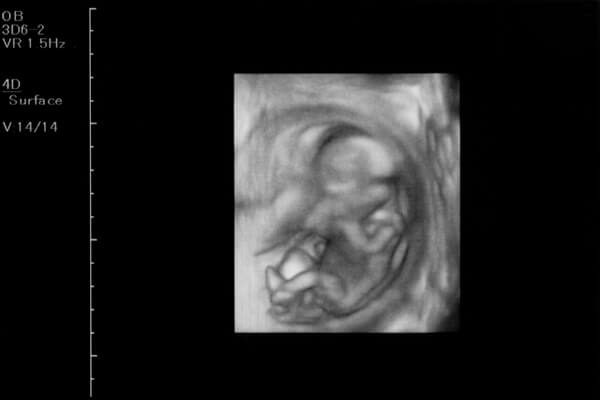

手足の骨や筋肉の発達が進むので、赤ちゃんはママの子宮の中で体を曲げたり、伸ばしたり、キックをしたりして元気に動いています。

妊娠12週目では、胎動を感じるのはまだ先になりますが、超音波検査ではそんな様子を見ることができるかもしれませんね。

顔のパーツもできあがり始め、目や鼻のつくりも細かくなってきます。妊娠12週目の頃はまだ音は感じられませんが、耳の形も整ってきます。